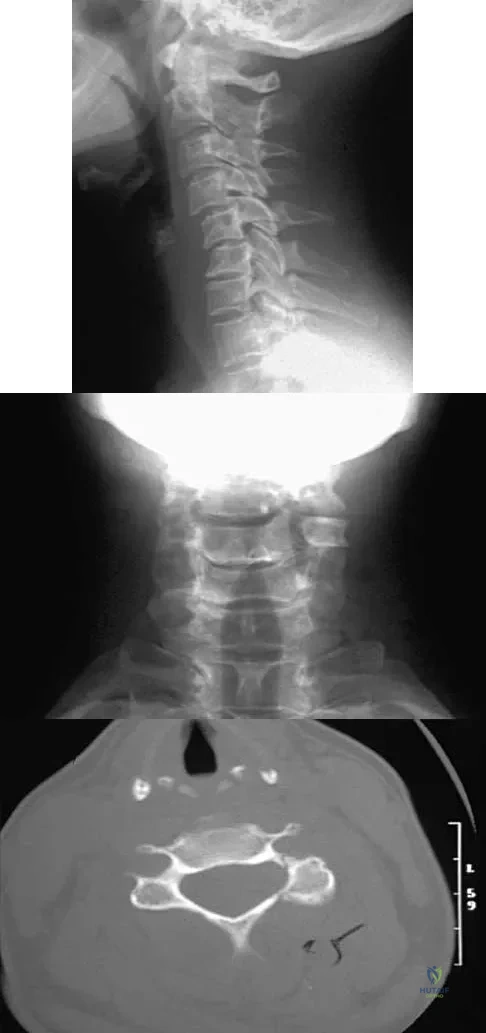

Question 66

A 53-year-old woman has severe neck and left shoulder pain after a rollover motor vehicle accident. Radiographs and a CT scan of the cervical spine are shown in Figures 34a through 34c. Management should consist of

Explanation